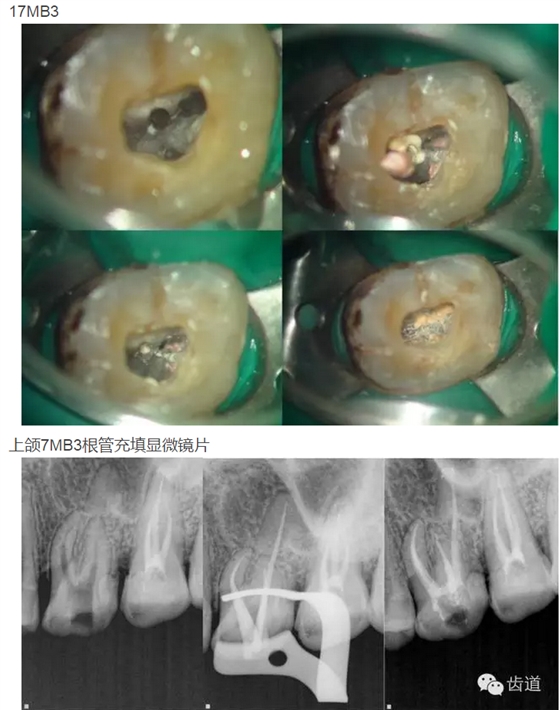

上頜第二磨牙:與上頜第一磨牙相似,多為3根管,偶見雙鄂根管;